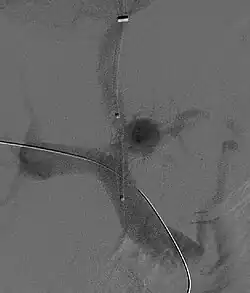

-

Magnetic resonance imaging of portal hypertension -

Portal hypertension due to cirrhosis resulting in revascularization of the umbilical vein

Ultrasonography (US) is the first-line imaging technique for the diagnosis and follow-up of portal hypertension because it is non-invasive, low-cost and can be performed on-site.[12]

A dilated portal vein (diameter of greater than 13 or 15 mm) is a sign of portal hypertension, with a sensitivity estimated at 12.5% or 40%.[13] On Doppler ultrasonography, a slow velocity of <16 cm/s in addition to dilatation in the main portal vein are diagnostic of portal hypertension.[14] Other signs of portal hypertension on ultrasound include a portal flow mean velocity of less than 12 cm/s, porto–systemic collateral veins (patent paraumbilical vein, spleno–renal collaterals and dilated left and short gastric veins), splenomegaly and signs of cirrhosis (including nodularity of the liver surface).[12]

The hepatic venous pressure gradient (HVPG) measurement has been accepted as the gold standard for assessing the severity of portal hypertension. Portal hypertension is defined as HVPG greater than or equal to 5 mm Hg and is considered to be clinically significant when HVPG exceeds 10 to 12 mm Hg.[15]